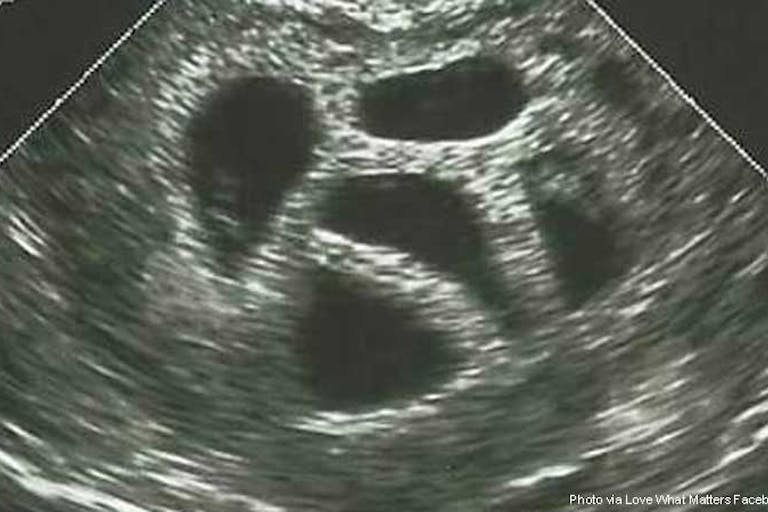

Susan makes a powerful connection in her Facebook posts by putting two pictures next to each other. The first is a fuzzy, black and white sonogram image of five unborn babies. The second is a picture of the day those five babies graduated from high school. Susan writes, “After graduation, three joined the military to serve our country and two are pursuing careers in the medical field. They are all responsible adults who love God and make this world a better place.” In the debate about abortion, there are few images as powerful as the ultrasound: the undeniable proof that the child in the womb is human is there before our eyes. It becomes clear that the people happily celebrating their graduation are the very same people who were crowded into their mother’s womb.